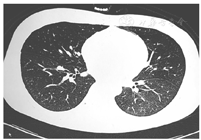

7月10日(化疗后第8天)血常规:白细胞计数1.58 × 109/L,中性粒细胞计数1.09 × 109/L,血红蛋白61 g/L,血小板计数17 × 109/L,当日11:20患者出现咳嗽,咳少量白痰带血丝,余未见出血,亦无呼吸气促等其他不适,予完善G试验,并予止咳糖浆对症处理。18:30患者咳嗽加重,并咳血2次,量约15 ml,予床边监测,血压118/72 mmHg(1 mmHg=0.133 kPa),脉搏105次/min,动脉血氧饱和度0.71,双侧中下肺可闻及细啰音,立即予4 L/min中流量给氧,动脉血氧饱和度升至0.94,查血常规:白细胞计数3.34 × 109/L,中性粒细胞计数3.1 × 109/L,血红蛋白50 g/L,血小板计数10 × 109/L;凝血功能:活化部分凝血活酶时间正常,凝血酶原时间18.6 s,纤维蛋白原3.65 g/L,降钙素原0.24 μg/L,C反应蛋白38.87 mg/L,B型脑钠肽前体1 503 ng/L,血气分析提示Ⅰ型呼吸衰竭,胸腹CT可见右肺上叶后段、左肺上叶尖后段、左肺舌段、右肺中叶、双肺下叶弥散多发斑片状阴影及磨玻璃影,边缘模糊,腹部重要脏器未见明显异常,考虑双肺多发炎性反应,并肺泡内积血(图2)。诊断:弥漫性肺泡出血。立即停用维甲酸、重组人粒细胞刺激因子及重组白细胞介素-11,予甲泼尼龙琥珀酸钠500 mg静脉滴注,并予无创呼吸机辅助通气,头孢哌酮钠舒巴坦钠、利奈唑胺、伏立康唑抗感染,垂体后叶素止血,以及成分血输注。次日患者临床情况稳定,床旁胸片与CT对比大致相似,完善床边纤维支气管镜检查并行肺泡灌洗,镜下各支气管未见出血,多肺段灌洗见血性灌洗液,常规留取标本送检及培养。